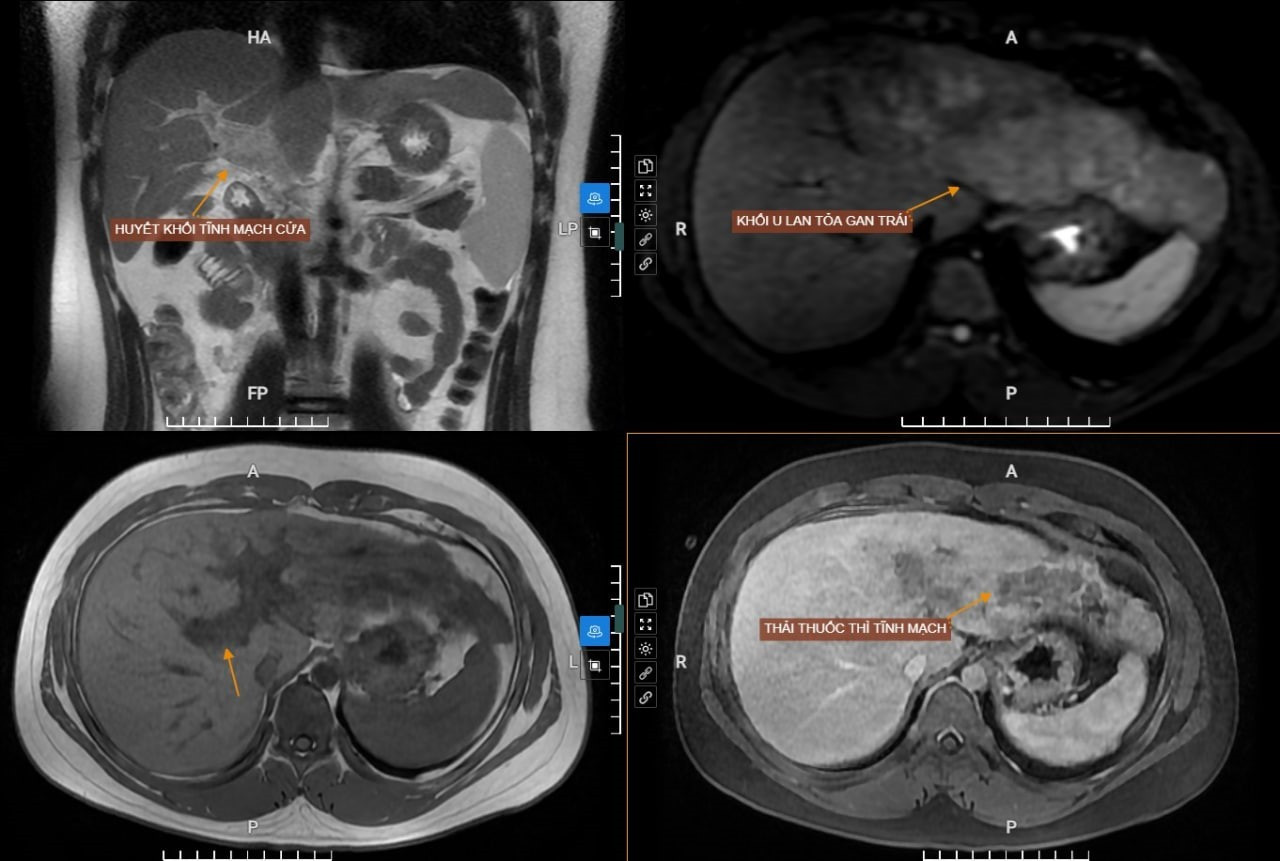

Kết quả siêu âm phát hiện nhiều nốt tăng âm trong gan, nhu mô gan thô kèm theo lách to. Sau đó, bệnh nhân được chỉ định chụp MRI ổ bụng có tiêm thuốc đối quang từ để đánh giá chi tiết các tổn thương. Kết quả phát hiện đám tổn thương lan tỏa không rõ ranh giới vùng nhu mô gan phải.

Sau khi tiến hành hội chẩn, các bác sĩ kết luận đây là khối ung thư gan lan tỏa nhu mô gan phải, có xâm lấn và gây huyết khối tĩnh mạch cửa.